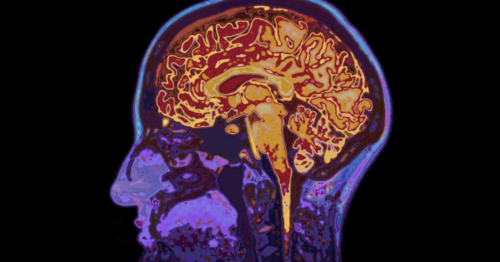

World’s Most Detailed Brain Map Built From A Grain Of Brain Tissue

The mission of Obama’s BRAIN Initiative in 2013 was to map the human brain. Twelve year later scientists have mapped 200,000 cells and 523 million synapses of mouse brain, smaller than a grain of sand. That’s all! After billions of dollars and countless man hours, note that they are not one inch closer to figuring […]